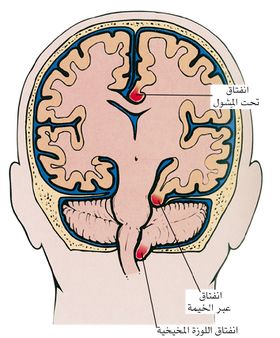

ويقسم الانفتاق الدماغي إلى أنواع حسب مكان حدوثه، منها الأنواع الرئيسة الآتية:

الشكل (1) انفتاق النسيج الدماغي

ـ الانفتاق تحت المشول :subfalcine herniation يحدث عندما يؤدي توسع أحد نصفي الكرة المخية إلى اندفاع التلفيف الحزامي cingulate gyrus وانحشاره تحت مشول منجل المخ falx cerebri (وهذا الأخير هو أحد الحواجز الصلبة المذكورة أعلاه). وكثيراً ما يترافق ذلك بانضغاط فروع الشريان المخي الأمامي، ولأن هذا الشريان يروي المنطقة من الدماغ المسؤولة عن حركة الطرف السفلي المقابل، فإن هذا الانفتاق يترافق عادة مع حدوث ضعف في الطرف السفلي.

ـ الانفتاق عبر الخيمة transtentorial herniation (أو الانفتاق المحجني uncal herniation): يحدث عندما ينضغط الجزء الأنسي من الفص الصدغي على الحافة الحرة للخيمة المخيخية. ينتج من ذلك انضغاط العصب الثالث المحرك للعين مما يسبب توسع الحدقة واضطراباً في حركات العين في ذلك الجانب. وكثيراً ما ينضغط الشريان المخي الخلفي مما يؤدي إلى اضطرابات معينة في الرؤية، وقد تحدث في مراحل متقدمة من الإصابة آفات نزفية في جذع الدماغ.

ـ انفتاق اللوزة المخيخية :tonsillar herniation المقصود به انزياح اللوزتين المخيخيتين وهبوطهما عبر الثقبة الكبرى (وهي فتحة كبيرة في أسفل الجمجمة). يحمل هذا الانفتاق خطورة كبيرة على الحياة لأنه يؤدي إلى انضغاط جذع الدماغ وإصابة مراكز التنفس في البصلة السيسائية.